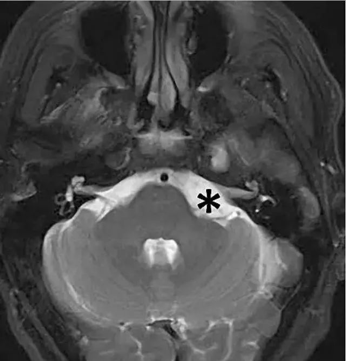

桥小脑角区 脑膜瘤 ,通常压迫周围许多重要神经血管、小脑甚至脑干,大肿瘤,手术难度大,手术不慎易残留肢体瘫痪、面瘫、听力损伤等。完整切除桥小脑角区脑膜瘤且不伤及...